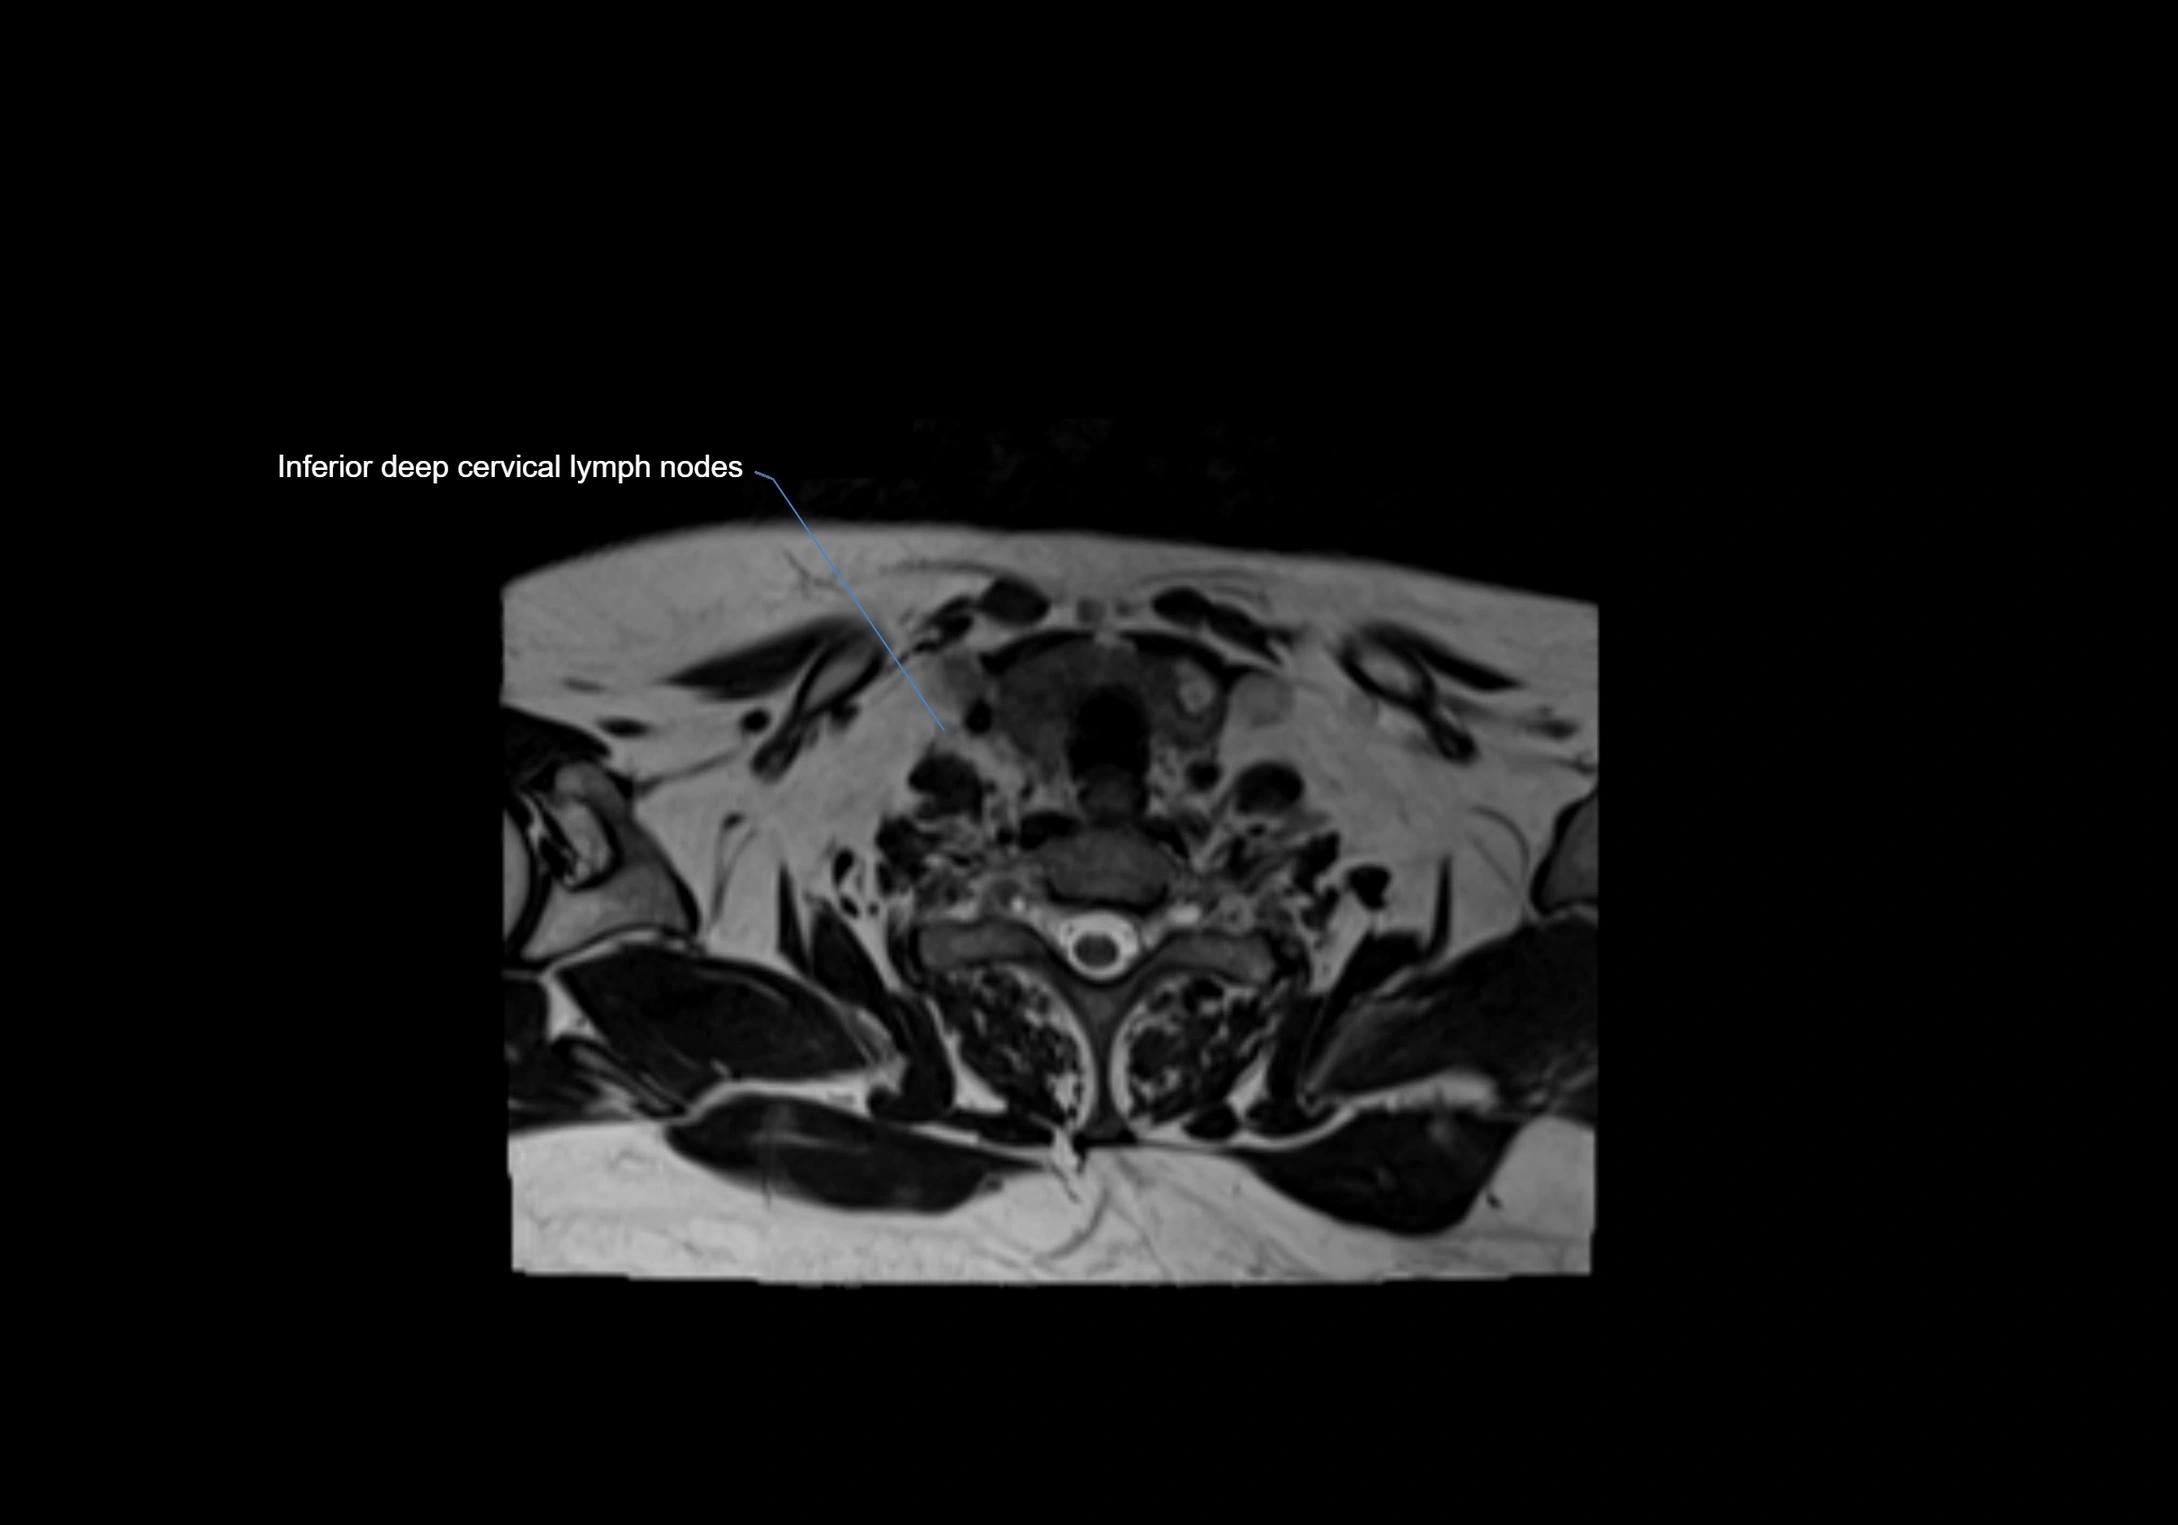

MRI Appearance

T1-weighted images:

• Normal accessory nodes appear as small, oval hypointense to intermediate signal structures within subcutaneous fat

• Surrounded by hyperintense fat, enhancing contrast for visualization

• Pathological nodes may appear enlarged or rounded, sometimes with cortical thickening

MRI images

image